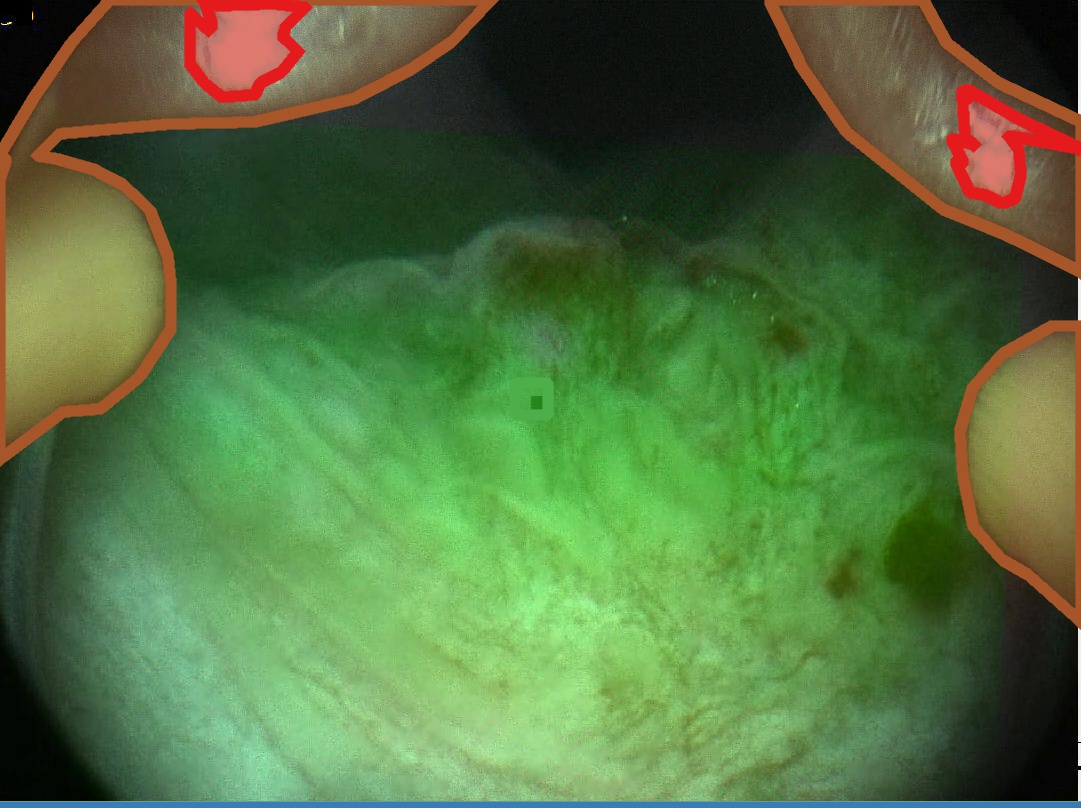

With the EAD Challenge we aimed to establish a first large and comprehensive dataset for “Endoscopy artifact detection” (see Fig. 1). The provided data was assembled from 6 different centers worldwide: John Radcliffe Hospital, Oxford, UK; ICL Cancer Institute, Nancy, France; Ambroise Parè Hospital of Boulogne-Billancourt, Paris, France; Instituto Oncologico Veneto, Padova, Italy; University Hospital Vaudois, Lausanne, Switzerland and the Botkin Clinical City Hospital, Moscow. This unique endoscopic video frame dataset is multi-tissue (gastroscopy, cystoscopy, gastrooesophageal, colonoscopy), multi-modal (white light, fluorescence, and narrow band imaging), is inter patient and encompasses multiple populations (UK, France, Russia, and Switzerland). Videos were collected from patients on a first-come-first-served basis at Oxford, with randomized sampling at French centres and only cancer patients were selected at the Moscow centre. Videos at these centres were acquired with standard imaging protocols using endoscopes built by different companies, Olympus, Biospec, and Karl Storz. The dataset was built randomly mixing the collected data with no exclusion criteria. All images have been carefully anonymised. No patient information should be visible in this data. A comprehensive open-source software222Useful tools for this dataset: https://sharibox.github.io/EAD2019/ have been established to assist the participants.

Examples for bounding box annotations for detection are shown in Fig. 2. It can be observed that while multiple boxes are annotated for several small specular areas; contrast, blur and instrument have relatively larger areas. Due to the overlap between two or more classes, the annotation by experts varied. This was minimized by following the detailed annotation protocol above. For semantic segmentation, a larger area mask was preferentially used to delineate locally very cluttered small specularity artifacts (see Fig. 3).